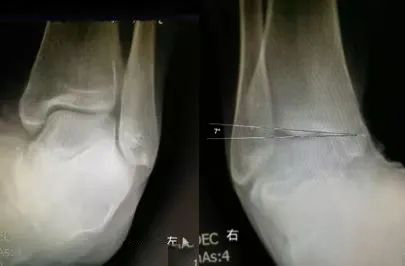

生活中,崴脚后常常忽视外固定的作用,特别是未存在撕脱骨折以及 X 线片假阳性者,踝关节应力位 X 片对于单纯的韧带损伤可发现踝关节不稳。

距骨倾斜角:内翻应力正位片中距骨相对于胫骨远端关节面倾斜角度 ≥ 9°,即可考虑踝关节不稳,但此时应考虑患者的职业,如芭蕾舞演员可存在足踝部韧带松弛

两则病例

28 岁青年女性,约 2 年前左踝首次发生崴脚,未行外固定处理,近 1 年来左踝间断多次崴脚,双侧踝关节应力正位片测量距骨倾斜角,左侧为 10°,右侧 4°,左侧应力位状态下感疼痛,右侧无不适感,考虑左侧踝关节不稳。

30 岁青年女性,1 年前右踝首次发生崴脚,未行外固定,伤后右踝间断数次崴脚,双侧踝关节应力正位片测量距骨倾斜角,左侧为 0°,右侧 7°,右侧虽尚不能诊断踝关节不稳,但距骨倾斜角增大,对比对侧仍考虑为崴脚后未外固定所致。